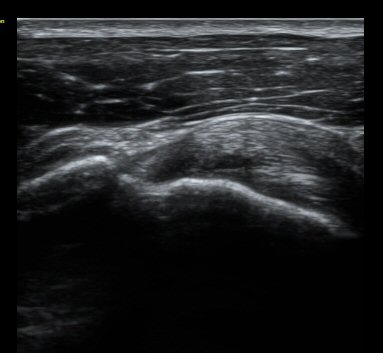

°ßºÀ ¿ÜÃø¿¡ ŽÃËÀÚ¸¦ ´ë°í ½ÃÇàÇÑ Ãæµ¹°Ë»ç¿¡¼­ °ßºÀ ¿ÜÃø¿¡ ¼ö¾×Àú·ù°¡ °üÂûµÇ¾ú´Ù.(±×¸² 9).

ÃÊÀ½ÆÄ°Ë»ç»ó °üÀý³» ¼ö¾×Àú·ù¸¦ º¸ÀÌÁö ¾Ê°í ÃÊÀ½ÆÄ °üÂûÇÏ ¿ÜÀü°Ë»ç¿¡¼­ °ßºÀ ¿ÜÃø¿¡

¼ö¾×Àú·ù°¡ °üÂûµÇ°í ȯÀÚÀÇ ¼öµ¿ÀûÀÎ ¿ÜÀü½Ã ÅëÁõÀ» º¸¿© Á¡¾×³¶³»¿¡ ÁÖ»çÄ¡·á¸¦ ½ÃÇàÇÏ¿´´Ù.